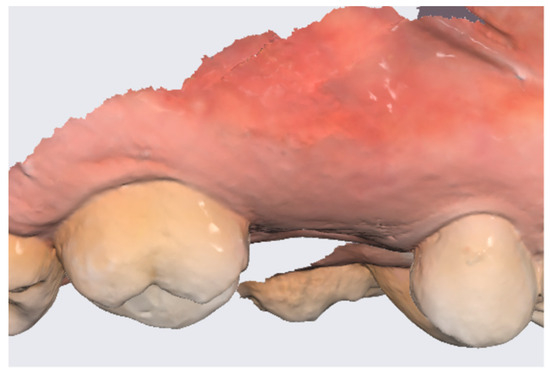

2.6. Case Presentation. Nano-HA Applied to Socket Preservation Procedures

3. Results